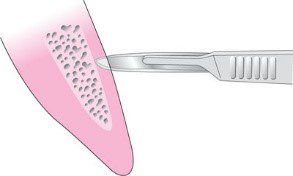

Đường rạch sắc bén là một trong những nguyên tắc quan trọng đối với thao tác phẫu thuật hiện đại. Các dụng cụ và kỹ thuật vi phẫu đã giúp đạt được mục tiêu này ở vùng đòi hỏi kỹ thuật cao như ở viền nướu. Tay cầm tròn, có kết cấu cho phép điều khiển tốt các lưỡi dao vi phẫu bằng tay (hình 2-8).

Hình dạng lưỡi dao truyền thống vẫn giữ một vị trí quan trọng trong phẫu thuật. Đặc biệt, lưỡi dao số 15 được thiết kế để cho phép tiếp xúc tốt với xương và rất có giá trị đối với các đường rạch dọc (hình 2-9).

Khi đường rạch dọc tiếp xúc với viền nướu, nên tạo một góc 90° bằng cách thay đổi độ nghiêng của lưỡi dao (hình 2-10) để dễ đóng vạt và tránh gây hoại tử do thiếu máu tại chỗ.

Thiết kế lưỡi số 12 có thể hữu ích cho các đường rạch trong khe nướu (hình 2-11).